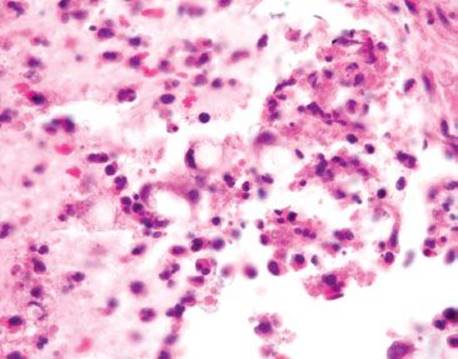

Figure 4.274 Endometriosis (ER immunostain). An ER immunostain shows diffuse nuclear reactivity in the indicated cells and a CD10 highlighted the stromal component (not shown), supporting the revised diagnosis of endometriosis. We have seen similar cases raise concerns for spindle cell sarcomas when the glandular elements were not present. Deeper sections and ancillary ER, PR, and CD10 are helpful diagnostic tools in challenging cases. Always consider endometriosis in a reproductive aged woman with a rectal mass.

Always consider endometriosis (a benign etiology) before malignancy in a reproductive aged woman with a rectal mass (Fig. 4.274).